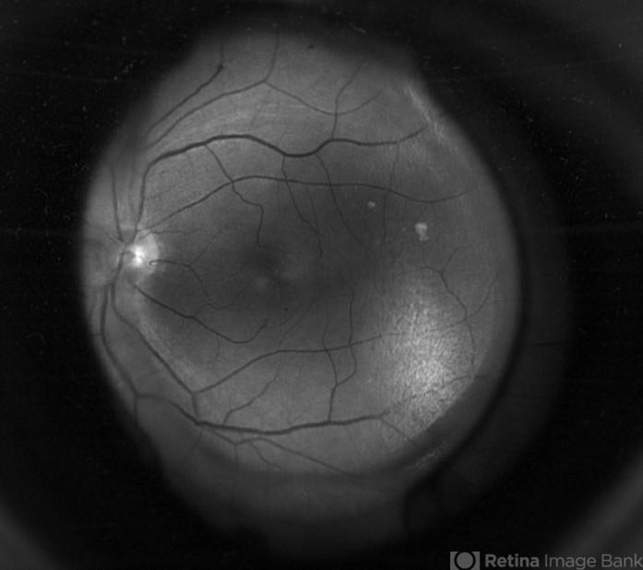

- retina, IOL, optos

- Fundus camera

- image through the principle axis with visibility of all structure in pathway .